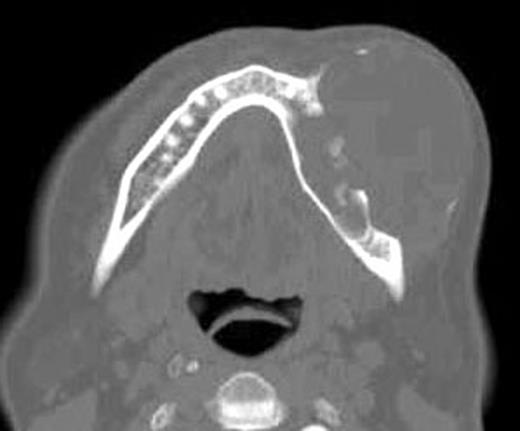

Preoperative axial CT view shows the lesion with destruction the medullar and buccal cortical portions of the left mandible.